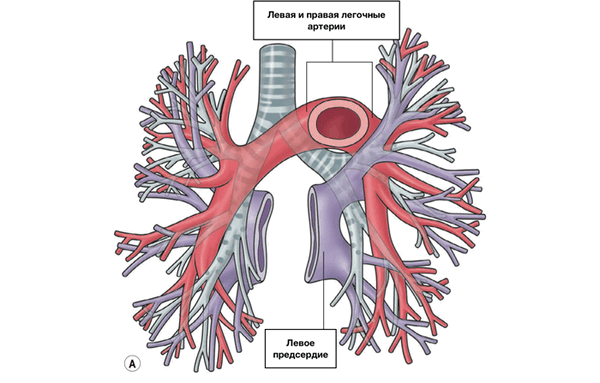

В период эмбриогенеза сосудистое русло легких образуется из спланхнического сплетения [4], которое не имеет связи с сердцем, однако соединяется с передними кардинальными и желточно-брыжеечными венами (рис. 2А).

По данным B.W. Eidem et al. [4], выпячивание левого предсердия соединяется с сосудистым руслом легких легочным венозным коллектором (общей легочной веной), который полностью соединяется с левым предсердием в течение первого месяца внутриутробного периода развития (рис. 2Б). При этом присоединении связи спланхнического сплетения, т.е. кардинальных и желточно-брыжеечных вен, с предсердием исчезают (рис. 2С). Легочная вена, вначале единая, делится на парные легочные вены (рис. 2Д). Эти вены также делятся на две ветви, каждая из них самостоятельно впадает в левое предсердие. Аномалии количества легочных вен проявляются их уменьшением до трех или двух или появлением добавочных легочных вен с нормальным или аномальным дренажом [3].

Рис. 2. Развитие легочных вен [4]. ЛОКВ – левая общая кардинальная вена, ПОКВ – правая общая кардинальная вена, ЖБВ – желточно-брыжеечная вена, ОЛВ – общая легочная вена, ЛП – левое предсердие, СС – спланхническое сплетение, ЛЛ, ПЛ – зачатки левого и правого легких